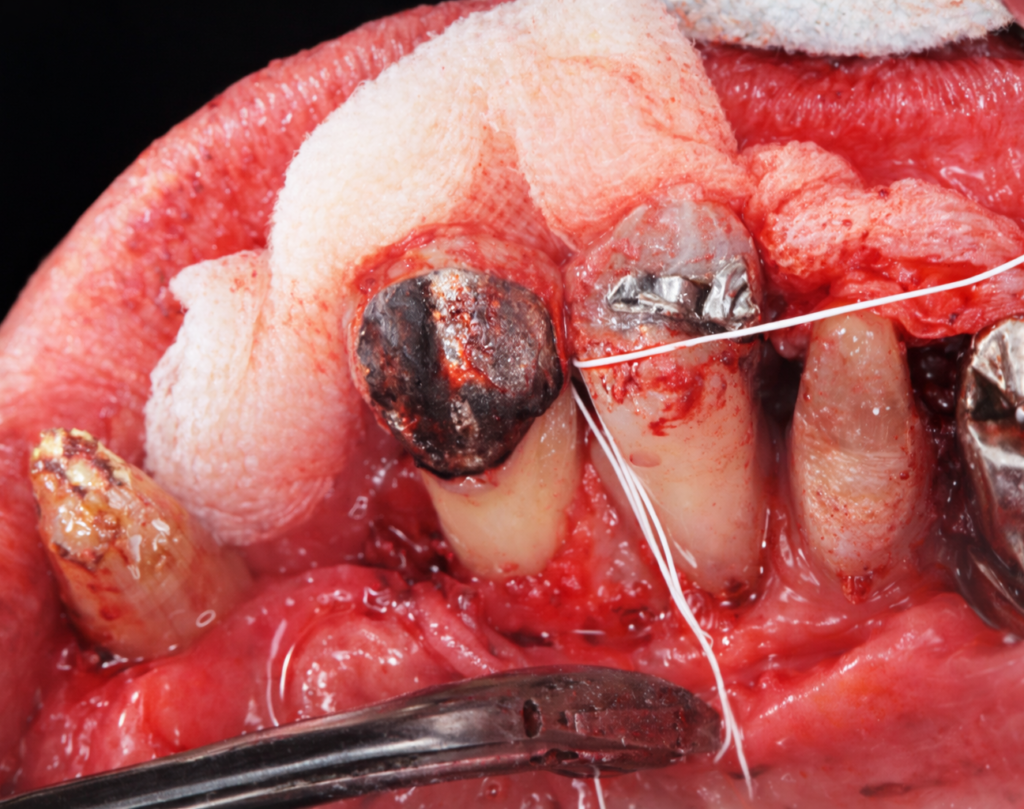

午前-45

67識の女性。上顎左側小臼歯の動揺を主訴として来院した.上顎左側 第一小臼歯の近心に深い歯周ポケットを認めた。歯周基本治療後、同部位にエナメルマトリックスタンパク質を用いた歯周外科処置を行うこととなった。 初診時のエックス線画像と不良肉芽組織除去後および縫合直前の口腔内写真を別に示す。

この手術で再生するのはどれか。2つ選べ。

a.歯槽骨

b.象牙質

c.エナメル質

d.セメント質

解答を見る

a.d